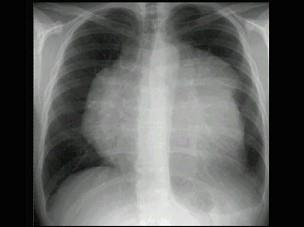

男,8岁,胸闷,气急,查体见颈静脉显露,胸片如图,最可能的诊断是 ( )A、房间隔缺损B、肺静脉异位引流C、心肌炎D、淋巴瘤E、心包积液

问题 男,8岁,胸闷,气急,查体见颈静脉显露,胸片如图,最可能的诊断是 ( )

选项 A、房间隔缺损 B、肺静脉异位引流 C、心肌炎 D、淋巴瘤 E、心包积液

答案 D